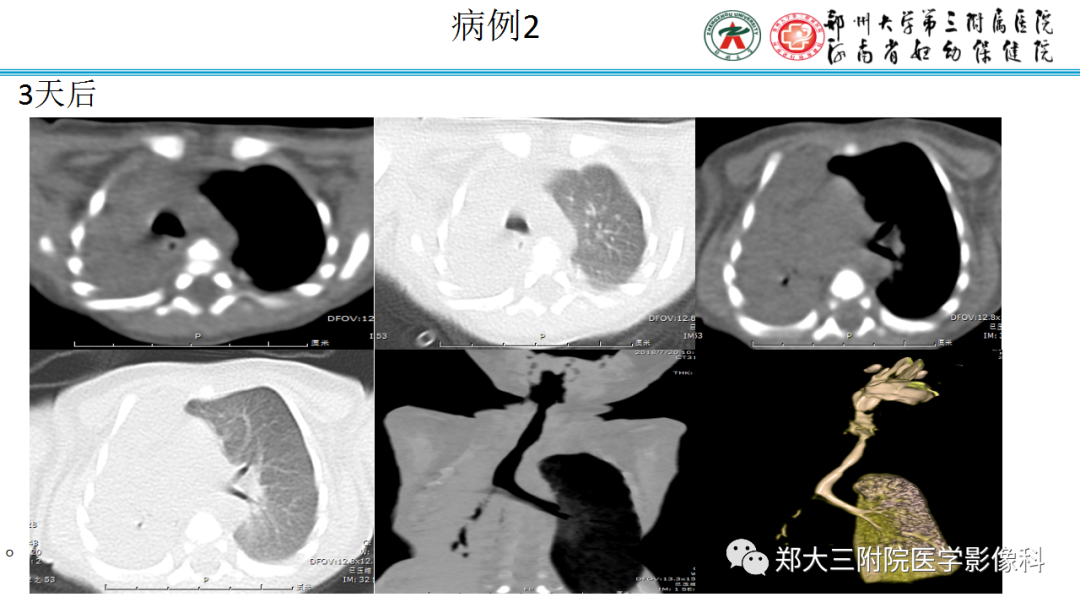

纵隔大细胞神经内分泌癌1例CT影像

纵隔大细胞神经内分泌癌1例CT影像  张力性纵隔气肿影像表现及严重度分级

张力性纵隔气肿影像表现及严重度分级  迅速增大的肺部结节,首先考虑良性,确诊需要肺穿